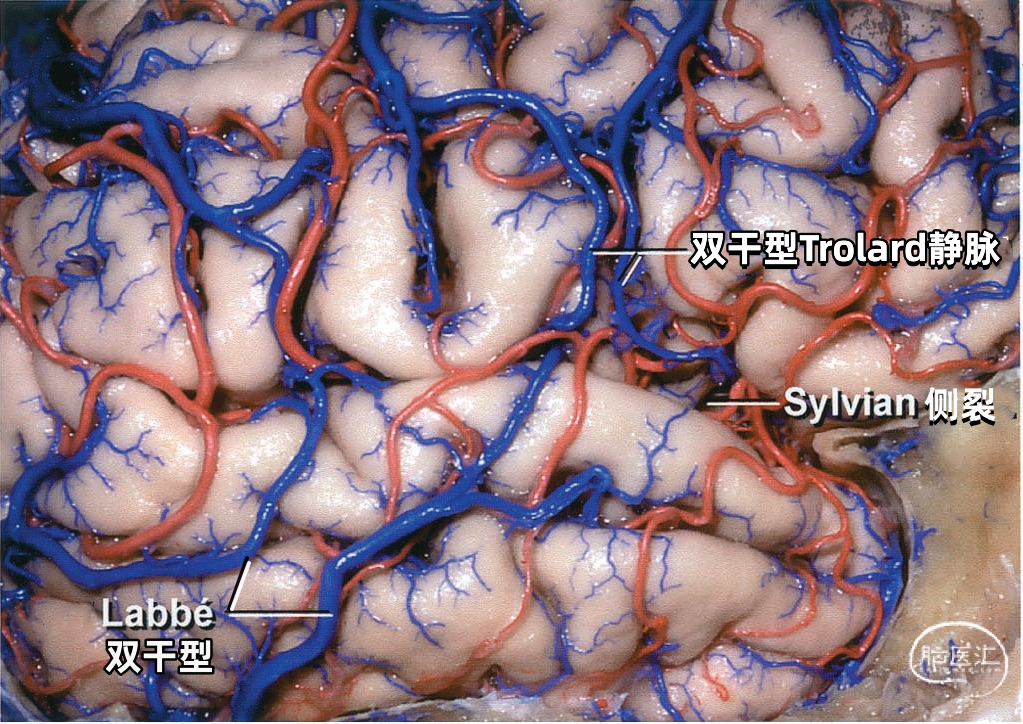

大脑外侧面最大的静脉是Trolard、Labbé、外侧裂浅静脉。 Trolard静脉是最粗大的吻合静脉,连接外侧裂静脉和上矢状窦。Labbé静脉则是连接外侧裂浅静脉和横窦的最粗大吻合静脉。外侧裂浅静脉沿外侧裂表面走行,而且主要沿蝶骨嵴汇入硬膜窦(蝶顶窦或海绵窦)。 虽然Trolard、Labbé静脉和外侧裂浅静脉大小可能相同,但更常见的是其中一支或两支血管比较粗大,而剩下的则细小甚至缺如。通常左右两侧血管的大小并不对称。

▼2.Labbé静脉

Labbé静脉也称下吻合静脉,是跨越颞叶外侧,连接外侧裂与横窦之间的最大吻合静脉。它通常起自外侧裂中部,行向后下,进入横窦前部。 Labbé静脉经过颞叶表面的位置有可能非常靠后甚至位于颞叶的最后界,或非常靠前达颞叶前1/3的外侧面。在此研究的20例半球中,12例Labbé静脉位于颞中静脉水平,6例位于颞后静脉水平,2例位于颞前静脉水平。有时会有两条Labbé静脉,其中后支通常会粗大一些。

▼3.外侧裂浅静脉

外侧裂浅静脉通常起自外侧裂后端,沿外侧裂唇行向前下。它可能以两支起始,但通常在沿蝶骨嵴进入静脉窦之前融合为一支。 外侧裂浅静脉接受额外侧裂静脉、顶外侧裂静脉和颞外侧裂静脉的回流,并经常与Trolard静脉和Labbé静脉相吻合。它穿经覆盖外侧裂前端的蛛网膜,在蝶骨嵴内侧部下方加入蝶顶窦,或直接进入海绵窦。它也有可能离开外侧裂,围绕颞极,进入中颅窝底的硬膜窦,引流入岩上窦,或通过蝶骨的小孔出颅与翼静脉丛相交通。 如果外侧裂浅静脉细小或缺如,则相邻的静脉将代替引流其区域。起自外侧裂上唇的静脉,向上引流加入进入上矢状窦的静脉;起自外侧裂下唇的静脉,直接向后下,汇入颞叶下方的硬膜窦。如果外侧裂浅静脉的中部缺如,则静脉前部加入蝶骨嵴的硬膜窦,而后部则加入Trolard和Labbé吻合静脉。

下图示(右侧半球)没有明显的外侧裂浅静脉。有双干型Labbé静脉从外侧裂到横窦。中央沟静脉和额后静脉的大小几乎相同,组成双干型Trolard静脉,连接外侧裂和上矢状窦。中央沟静脉下部走行于中央沟内。

下图示双干型Trolard静脉和双干型Labbé静脉引流外侧裂附近的大部分静脉。